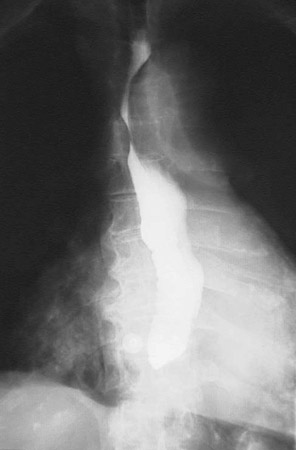

![]() | This radiograph taken following barium swallow demontrates a stricture in the lower esophagus, with pooling of the contrast above the point of stricture. Such stricture may complicate conditions such as scleroderma, gastroesophageal reflux disease, or carcinoma. |